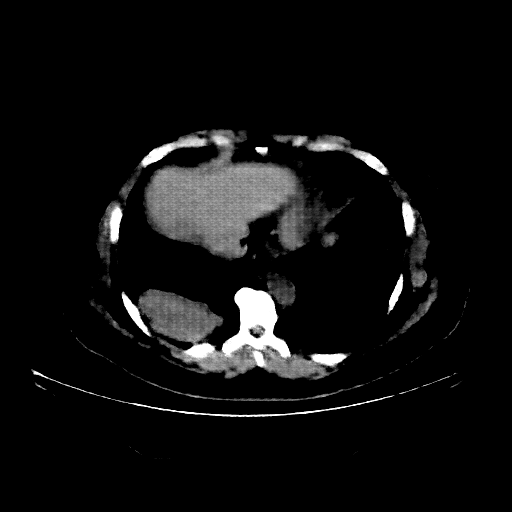

Reconstructed NATIVE CT scan (cycle consistency)

Full window (WL 1023.5, WW 4095 β†’ Low βˆ’1024, High +3071)

Actual HU range: [-1024.0, 631.9]